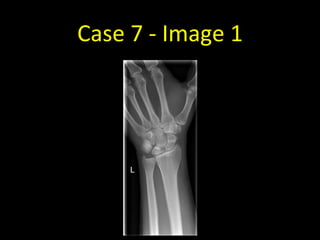

Case 7

• 34 year old with pain in the anatomical snuffbox

Case 7 - Image 1

• Scaphoid fractures can be notoriously

difficult to see. Four views are obtained

when a scaphoid fracture is suspected.

• A comminuted fracture of the waist of

the left scaphoid is visible on this

scaphoid series - this example is easier

to spot than most scaphoid fractures

• If a scaphoid fracture is still suspected

despite not being visible on radiographs,

the wrist should be immobilised and

repeat radiographs performed in 7-10

days at which time the fracture may be

more apparent.